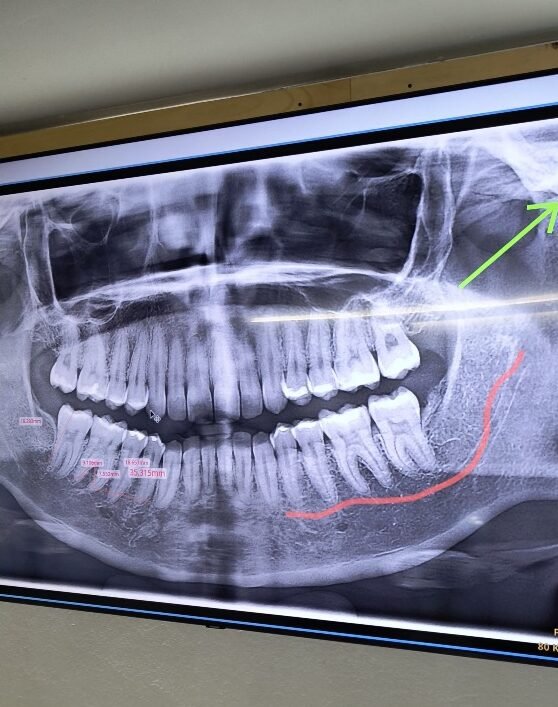

En Alaia Odontología iniciamos con una evaluación integral de tu salud bucal y estética facial. Analizamos la posición dental, la mordida, la forma de los dientes, el color, la relación con los labios y la armonía general del rostro. Utilizamos fotografías clínicas, estudios radiográficos y análisis digital para entender tu sonrisa de manera profunda. Durante esta etapa, te explicamos de forma clara qué se puede mejorar, qué resultados son realistas y si las carillas E-max son la mejor opción para ti. Este paso es clave para crear confianza y asegurar que el tratamiento sea seguro, funcional y alineado con tus expectativas estéticas.

Las radiografías por ejemplo son con una camarita de baja radiación. Muy recomendable